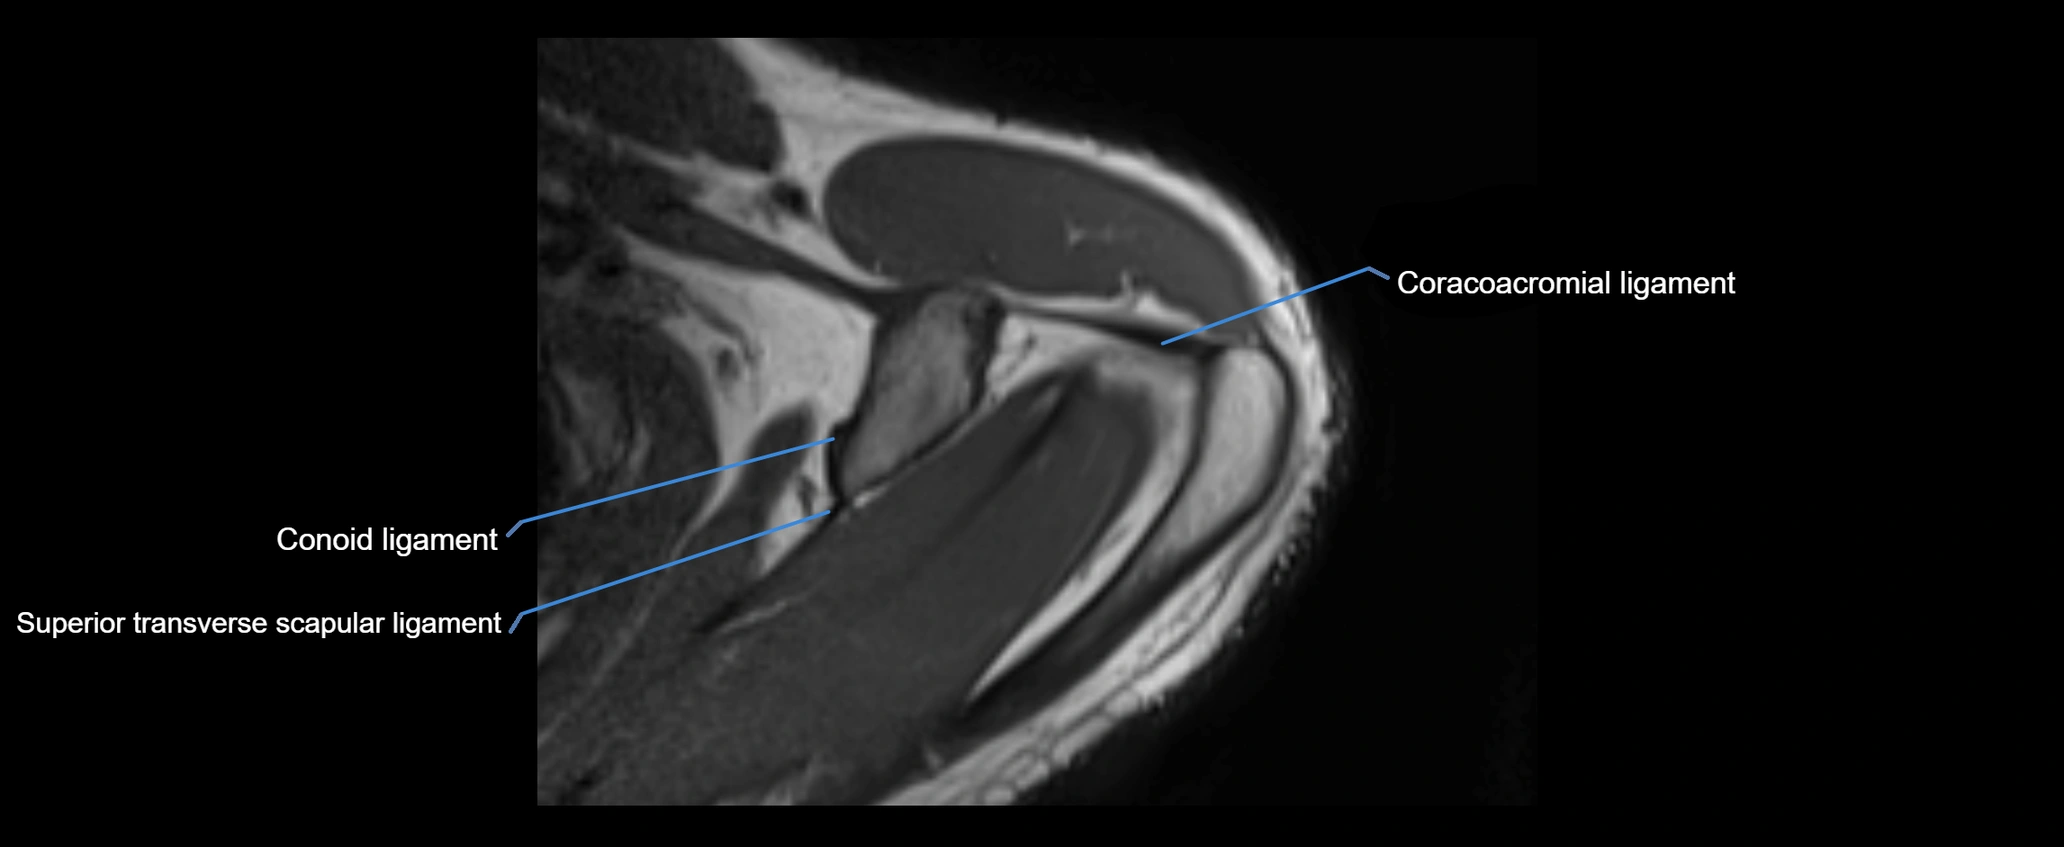

MRI images

image